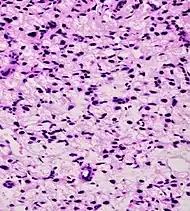

Microscopic characteristics

- Specific but relatively rare

- [notes 4]

- Collagenous micronodules[4]

- Glomerulations,[4] epithelial proliferations into one or more gland lumina, typically a cribriform tuft with a single attachment to the gland wall.[18]

- Perineural invasion.[4] It should be circumferential[18][notes 5]

- Angiolymphatic invasion[4]

- Extraprostatic extension [4]

- Relatively common and highly specific

- [4]

- Multiple nucleoli

- Eccentric nucleoli[4]

- Less specific findings.

- Mitoses (also seen in for example high-grade prostatic intraepithelial neoplasia (HGPIN) and prostate inflammation).[4]

- Prominent nucleoli[4]

- Intraluminal eosinophilic secretion[4]

- Intraluminal blue mucin[4]